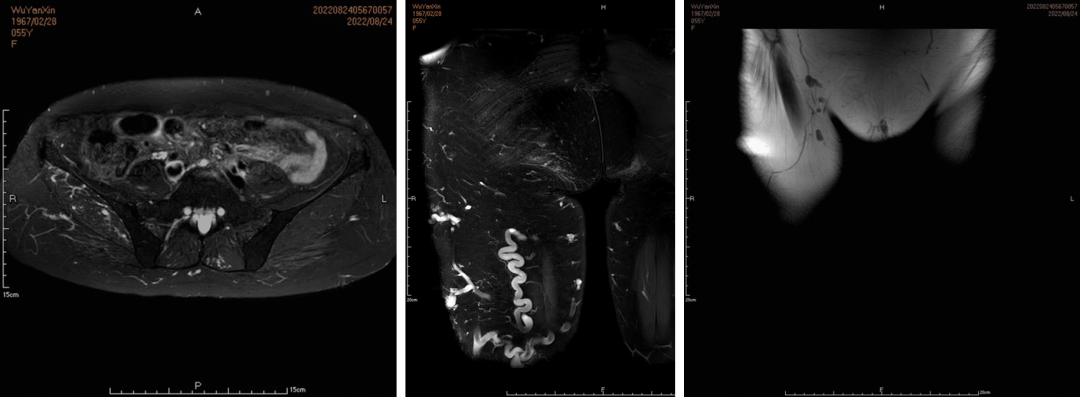

Sandwich技术优化-节约版

GLUBRAN替代Onxy;

双股静脉入路:可调弯鞘解决反流支;

减少可控圈以及微导管使用;

减少费用;

减少照射;

减少移位;

减少复发;

需解决技术问题:液体栓塞材料溢流。

示例(D-IIV)

示例(LOV+LCV)